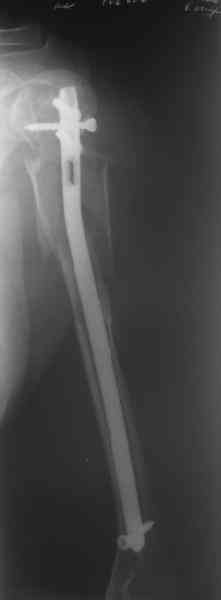

Здесь нет необходимости в серкляже. Вмешиваться на промежуточных отломках приходится, если есть угроза перфорации кожи, или промежуточный отломок попал в фасцию, как пуговица в петлю. В приложении сегментарный оскольчатый перелом плеча в проксимальном отделе, фиксированный больщеберцовым стержнем. Как видите, обошлось без серкляжа. Функция полная.

Пример отличный.

Вот что значит лечить перелом, а не рентгенограмму!

Александр, великолепные снимки! Вопрос - что за гвоздь?

Это укороченный большеберцовый стержень, которые делает предприятие "ЦИТО".

на синтезовский UTN похож))

Скажите пожалуйста, Александр Николаевич, почему Вы использовали большеберцовый гвоздь?

Доступные на тот момент гвозди для плеча имели худшие возможности фиксации в коротком проксимальном отломке.

Уважаемый Александр Николаевич! На продемонстрированных вами рентгенограммах имеется достаточно большое на мой взгляд смещение отломков после фиксации блокируемым гвоздем. На счет полной функции все понятно, а нет ли каких либо сосудистых расстройств конечности? Имею ввиду венозную недостаточность или лимфостаз.